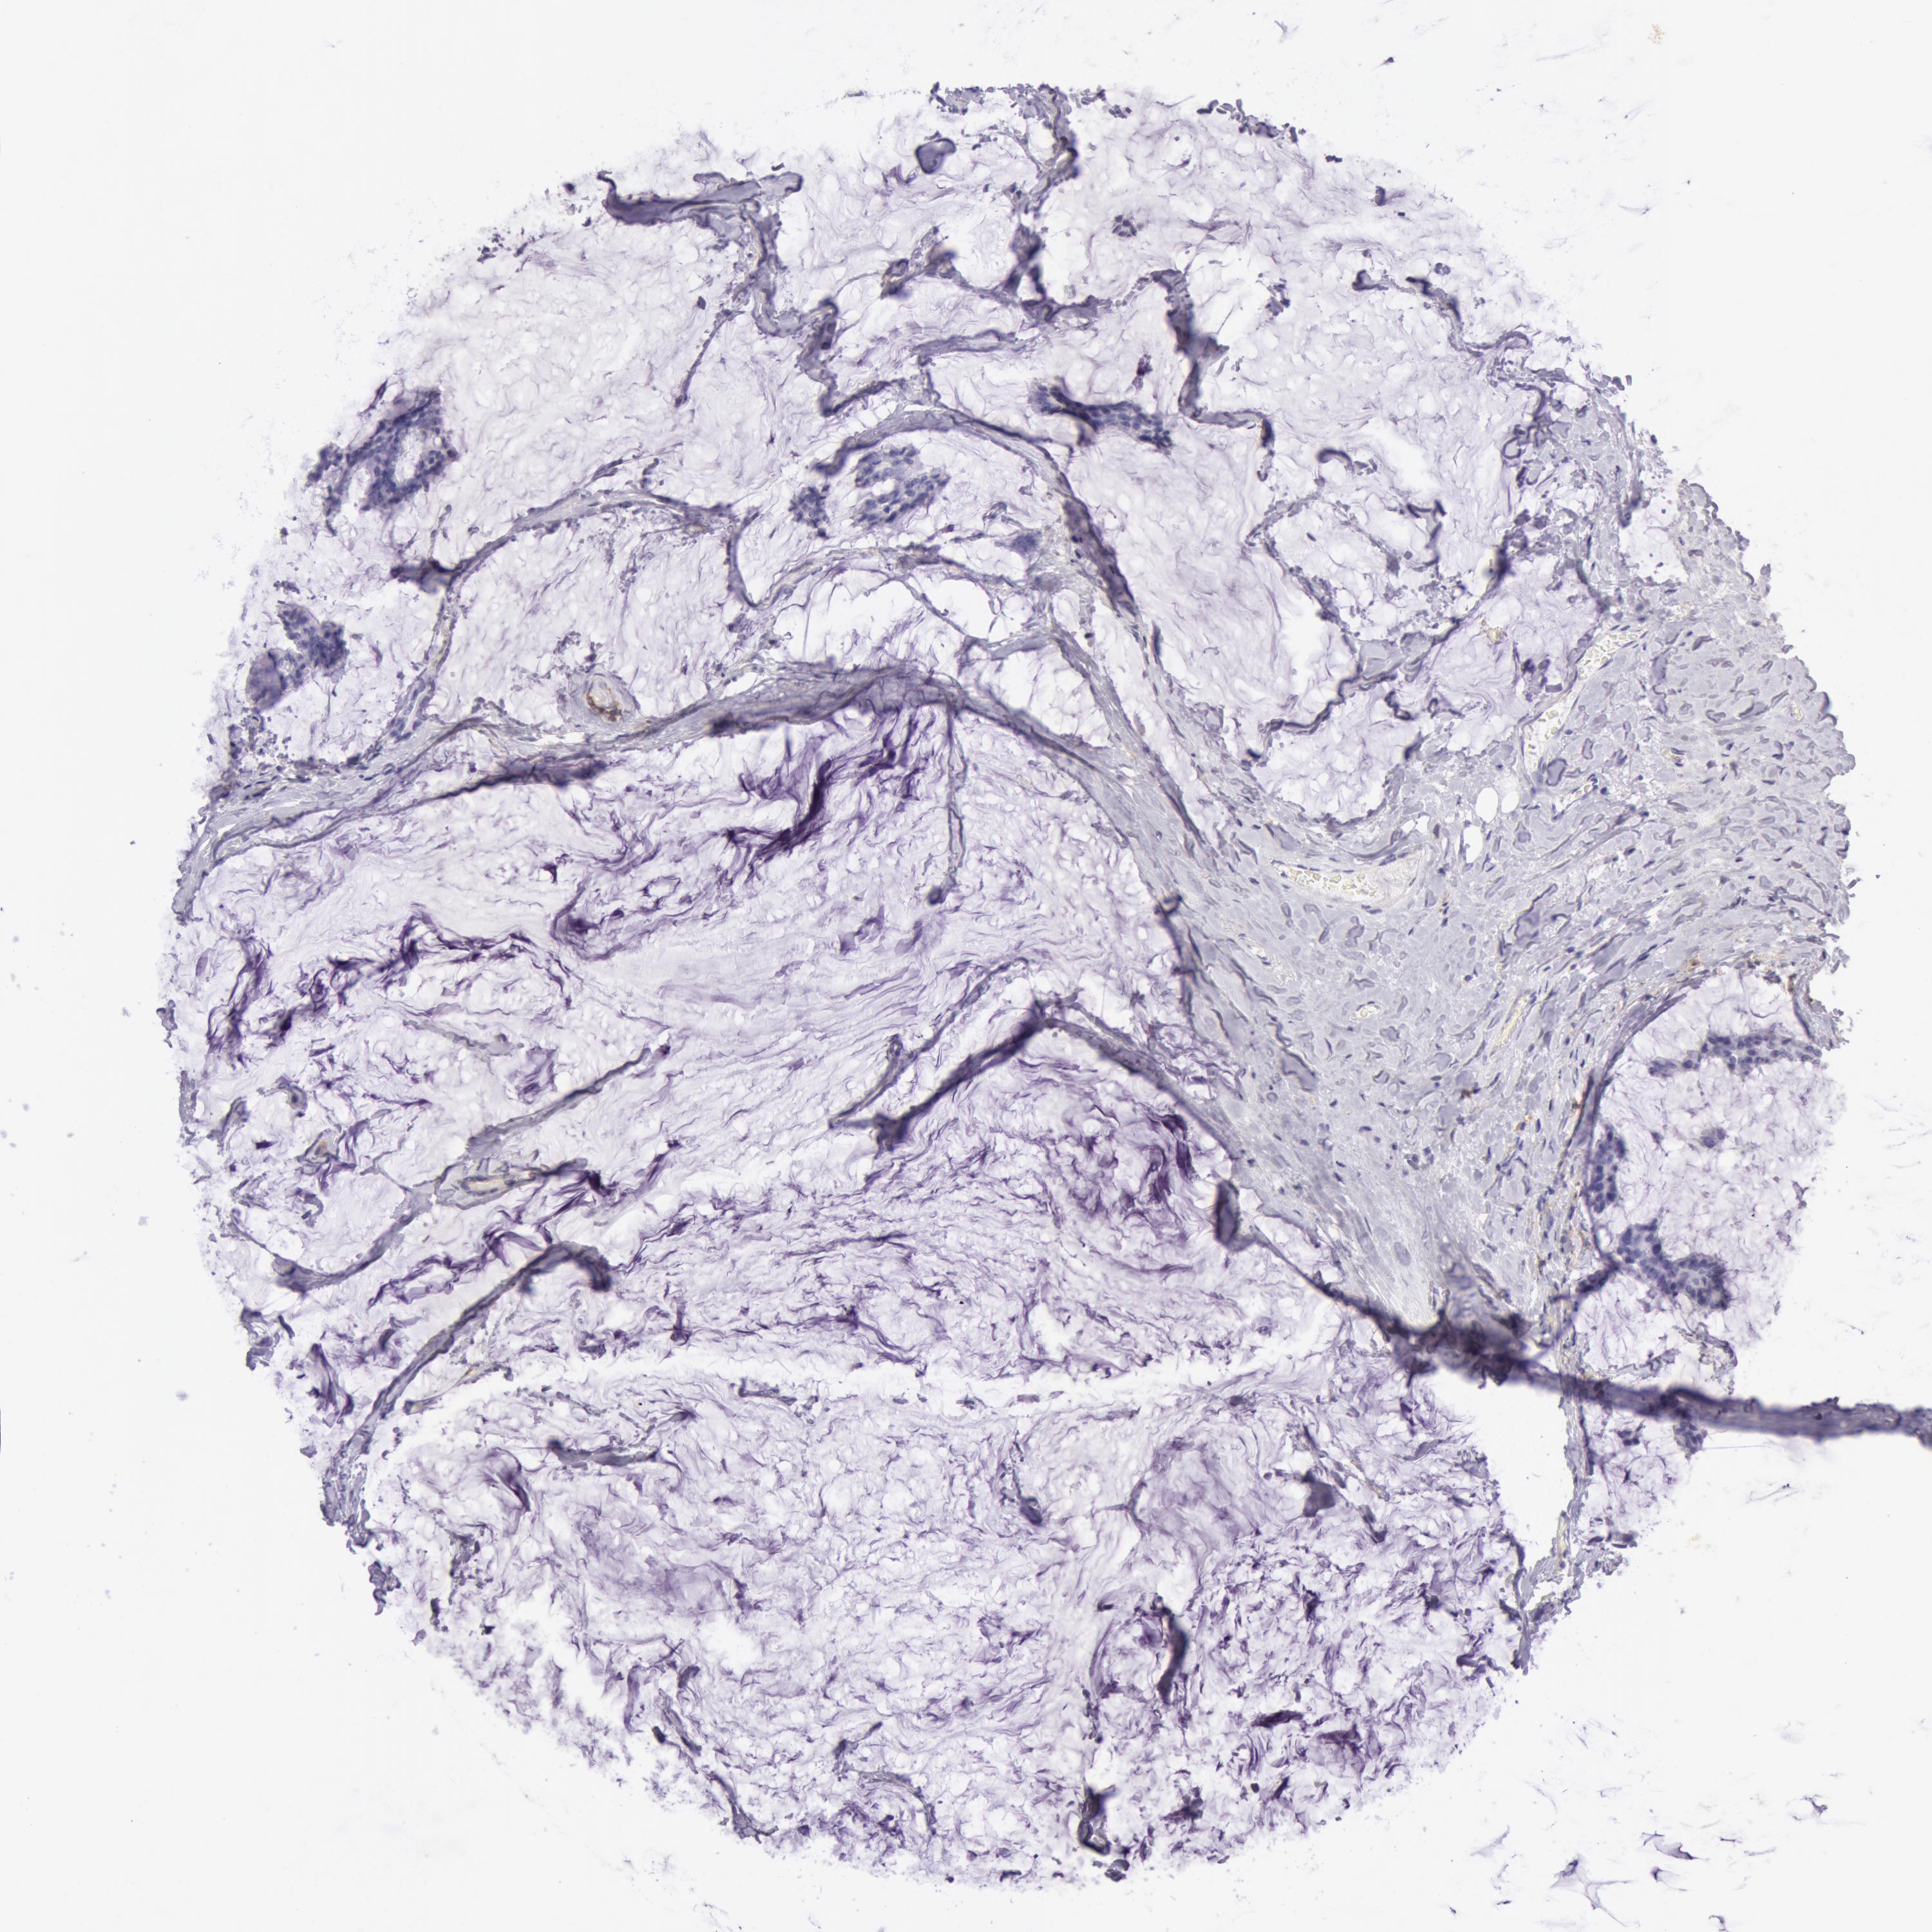

BRCA TCGA BRCA VALIDATION PROTEIN EXPRESSION

ANTIBODIES

AND

VALIDATION